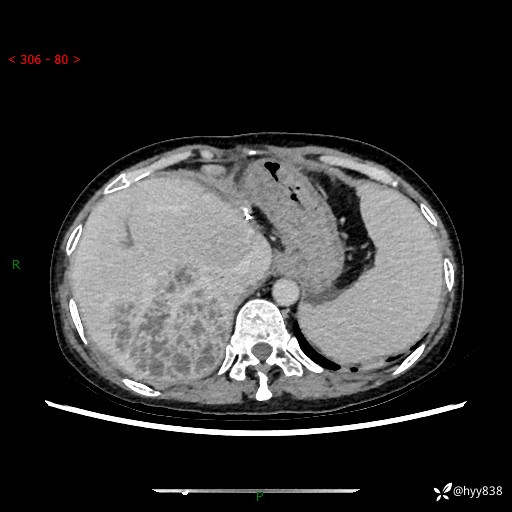

上腹部CT平扫